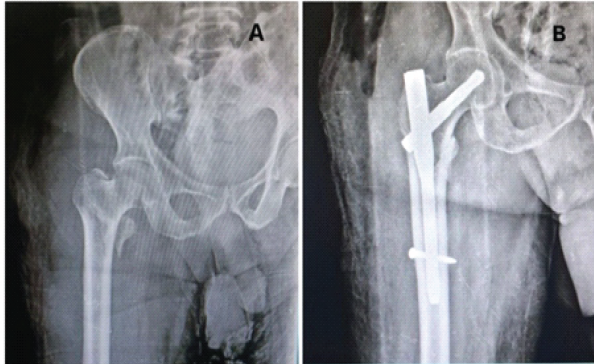

An 80-year-old male patient with TYPE 31-A2.1 pertrochanteric femur fracture of the right side (Fig. 3).

Figure 3: (a) Pre-operative anterior-posterior (A-P) view X-ray showing TYPE 31-A2.1 pertrochanteric femur fracture of the right side. (b) Post-operative A-P view X-ray showing pertrochanteric femur fracture fixed with short proximal femur nail.